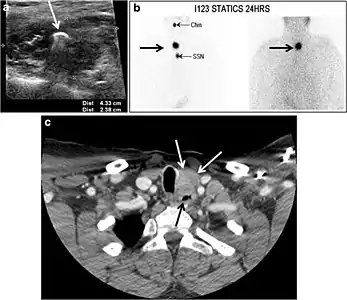

Fig. 18. Lingular thyroid in a 33-year-old male who presented with oropharyngeal bleeding. an Axial enhanced neck CT scan at the level of mandible demonstrates a 3 × 3 × 3.4 cm round, partly well-delineated, heterogeneously enhancing lesion (white arrow). It is predominantly on the left side of the oropharynx and to some extent at the mid part of the base of the tongue. The thyroid gland was normal (not shown). b Image of the anterior face and neck taken 20 minutes after Tc99m-Pertechnetate injection shows absent thyroid radiotracer uptake in normal thyroid anatomical location (black short arrows). There is an area of increased uptake (long black arrows) corresponding to the posterior tongue mass identified on CT scan.[1]